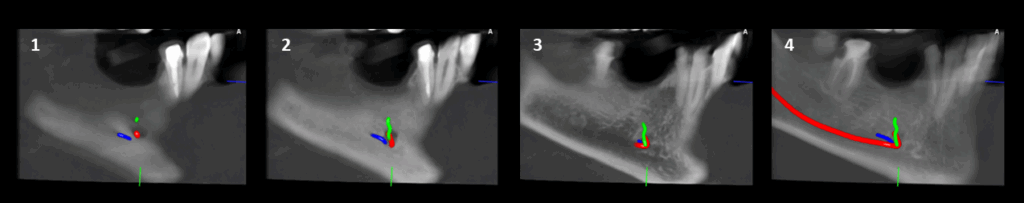

CORTES TANGENCIALES

En la ampliación imagenológica con tomografía computarizada de haz cónico, a nivel del cuerpo mandibular derecho, se identifican forámenes accesorios adicionales al agujero mentoniano principal. Se observa un segundo agujero mentoniano de menor diámetro, ubicado superior al principal, con trayecto cefálico. Además, se identifica un tercer agujero mentoniano localizado en posición distal respecto al foramen principal.

- Triple agujero mental (variante anatómica).

Si bien las radiografías panorámicas continúan siendo útiles como primera aproximación diagnóstica, presentan limitaciones importantes debido a la superposición de estructuras, la posible distorsión de la imagen o la orientación del foramen, que puede ocultar su presencia. En este caso, los múltiples agujeros mentonianos del lado izquierdo no fueron evidenciados en la radiografía panorámica. La tomografía computarizada de haz cónico permitió identificarlos con precisión, demostrando su valor como herramienta indispensable para el diagnóstico detallado y la planificación quirúrgica, especialmente en la colocación de implantes en esta región (2).

En este contexto, la evaluación tridimensional se convierte en un recurso imprescindible, ya que permite visualizar con exactitud variaciones anatómicas que pasan desapercibidas en estudios bidimensionales. La correlación entre los hallazgos en tomografía y los antecedentes de fallas anestésicas previas en la zona puede orientar al clínico hacia la explicación de bloqueos ineficaces, minimizando riesgos y permitiendo un abordaje quirúrgico y anestésico más seguro y predecible.